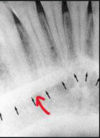

92

identify the anatomical structure below.

inverted "Y" - zygomatic process